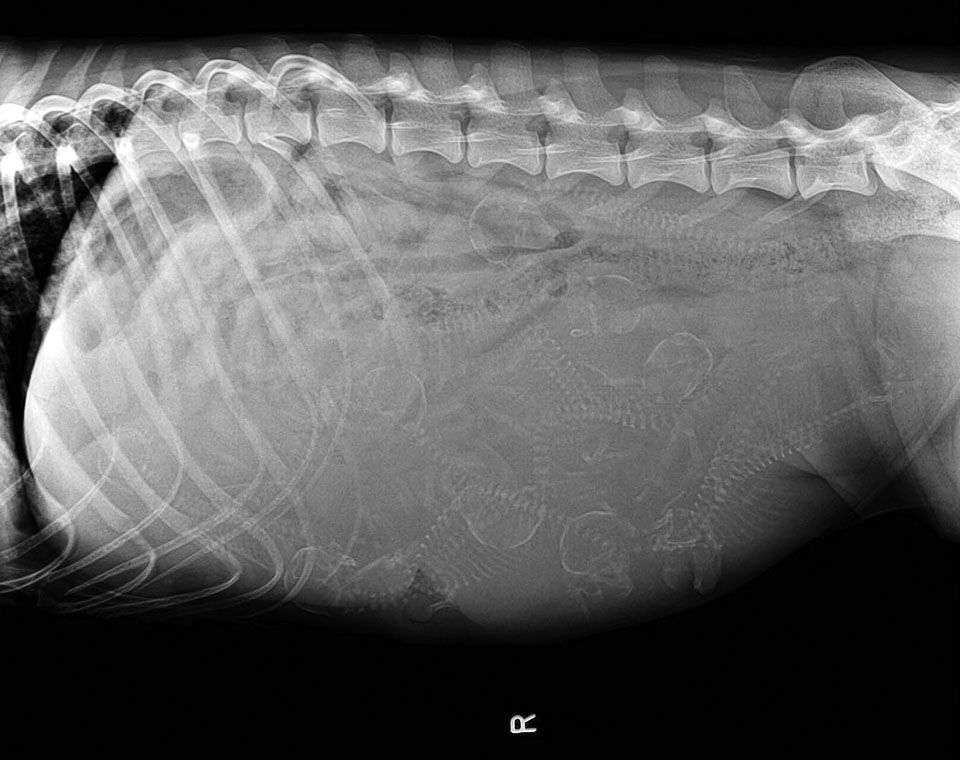

Are X-Rays Safe For The Mom And Puppies?

In response to the question of whether x-rays are safe for pregnant dogs, the answer is yes. However, x-rays are only performed after 45 days from conception when the puppies have completed their most critical development and can be fully seen on the x-ray. The exposure to radiation for both the mother and the puppies is minimal since only 1-3 x-ray views are taken. At our clinic, we use modern equipment with minimal radiation spillover, and our team wears protective gear during the process to prevent prolonged exposure.